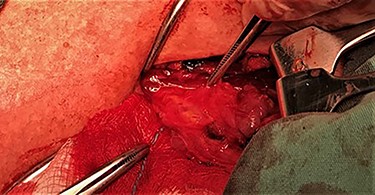

After a careful preparation of the anatomical structures of the neck and exposure of the thyroid gland, we proceeded to recognition of the parathyroid gland (Fig. 1). Then, glycerol solution was injected with a syringe of 2.5 ml and a needle of 26 gauges, to the loose connective tissue between the thyroid gland capsule and the parathyroid gland (Fig. 2). The amount that was administered was such as to produce the desired effect of tissue separation. By injecting the glycerol solution, the tissues swell, the size of the surgical field increases and the anatomical preparation of the parathyroid gland becomes simpler and with minimal parathyroid gland handling. A field like a glass is created, where the vasculature and the limits of the parathyroid gland are distinguished (Fig. 3). After that, a carefully dissection with a Mayo dissection scissor leaves the parathyroid gland intact. This technique is called TDSI.

Solution injection with a syringe of 2.5 ml and a needle of 26 gauges, to the loose connective tissue between the thyroid gland capsule and the parathyroid gland.